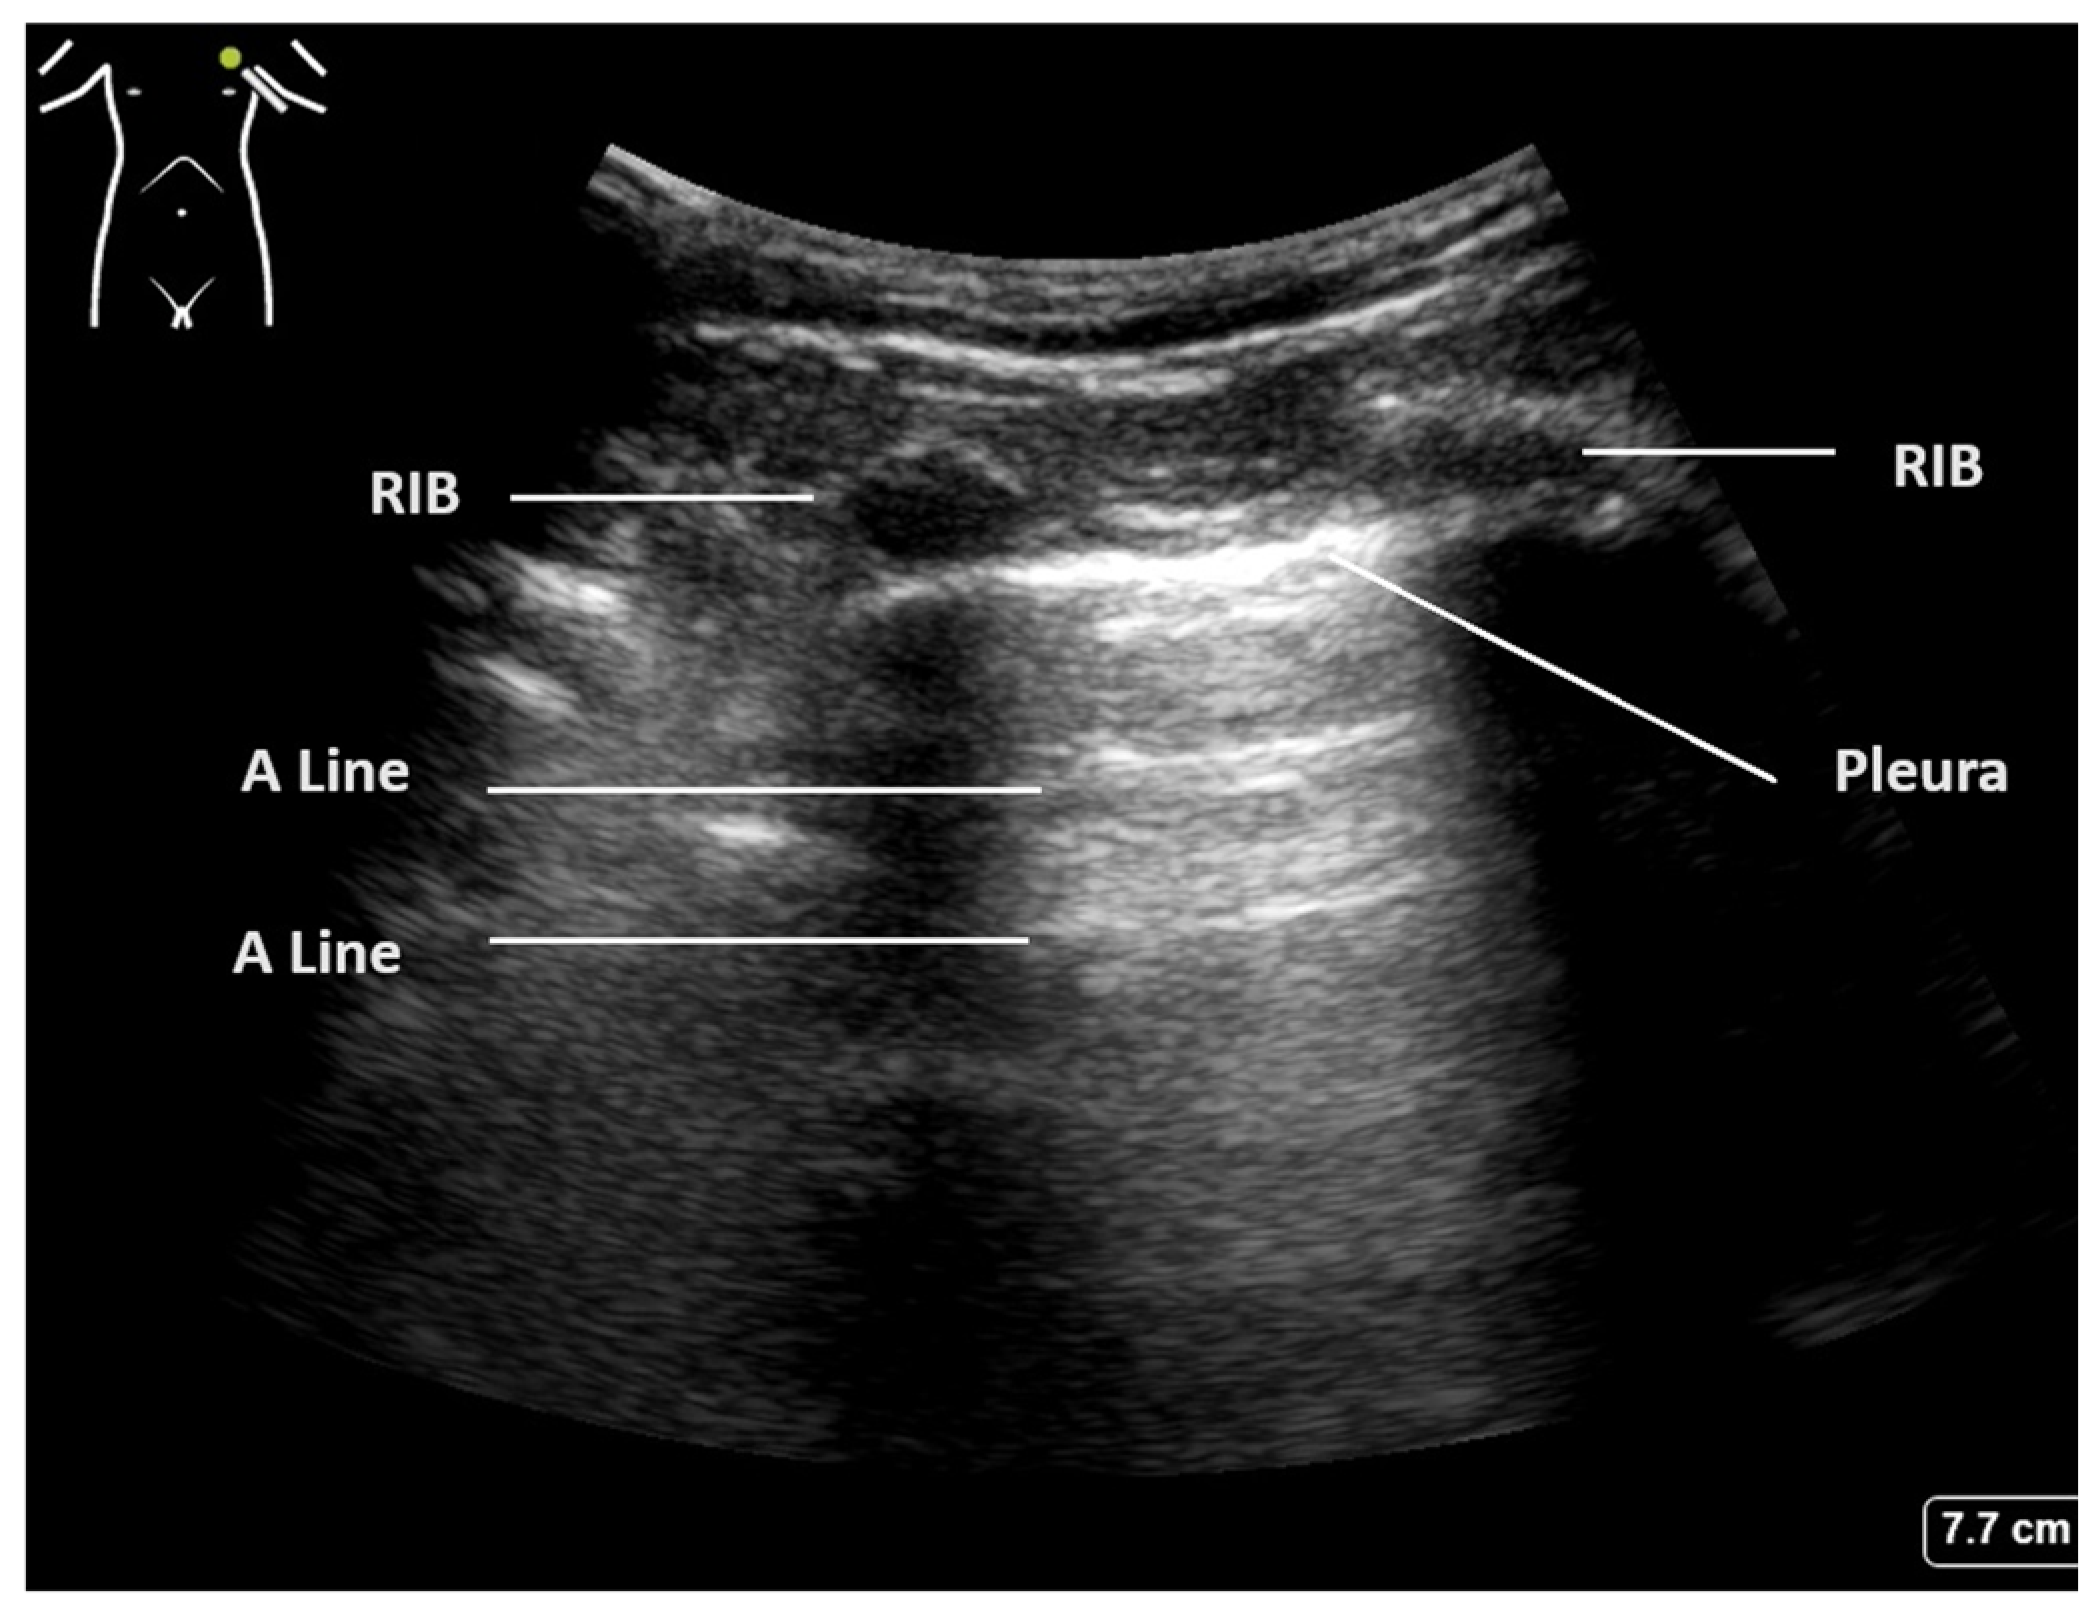

| Normal aerated lung | Movement of the pleural line with tidal ventilation Presence of A-lines (Figure 1) Maximum of 2 B-lines per image |